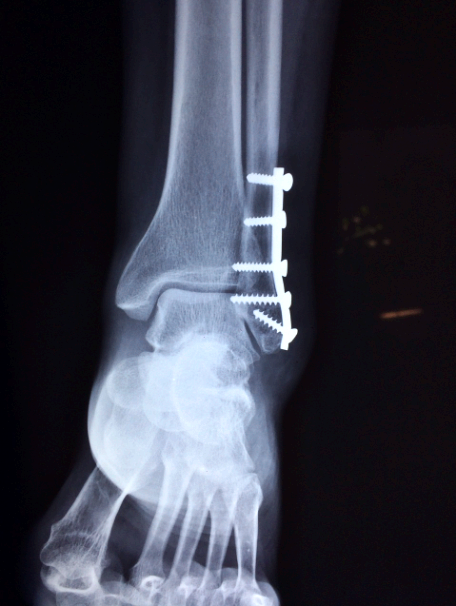

2. 부상당한 발의 꿈

일상에서 마주할 장애물이나 도전을 상징하며,

부상의 심각성은 문제의 크기를 나타낼 수 있습니다.

52. 발목이 부러지는 느낌을 받는 꿈은,

현재 진행 중인 일들이

중단될 수 있음을 시사합니다.

75. 발목이 부러지는 꿈은

계획하거나 상상하던 일이 예상치 못한 방향으로

전개될 수 있다는 것을 나타냅니다.

예상치 못한 상황에 대비하고,

유연하게 대처하는 능력이 필요합니다.